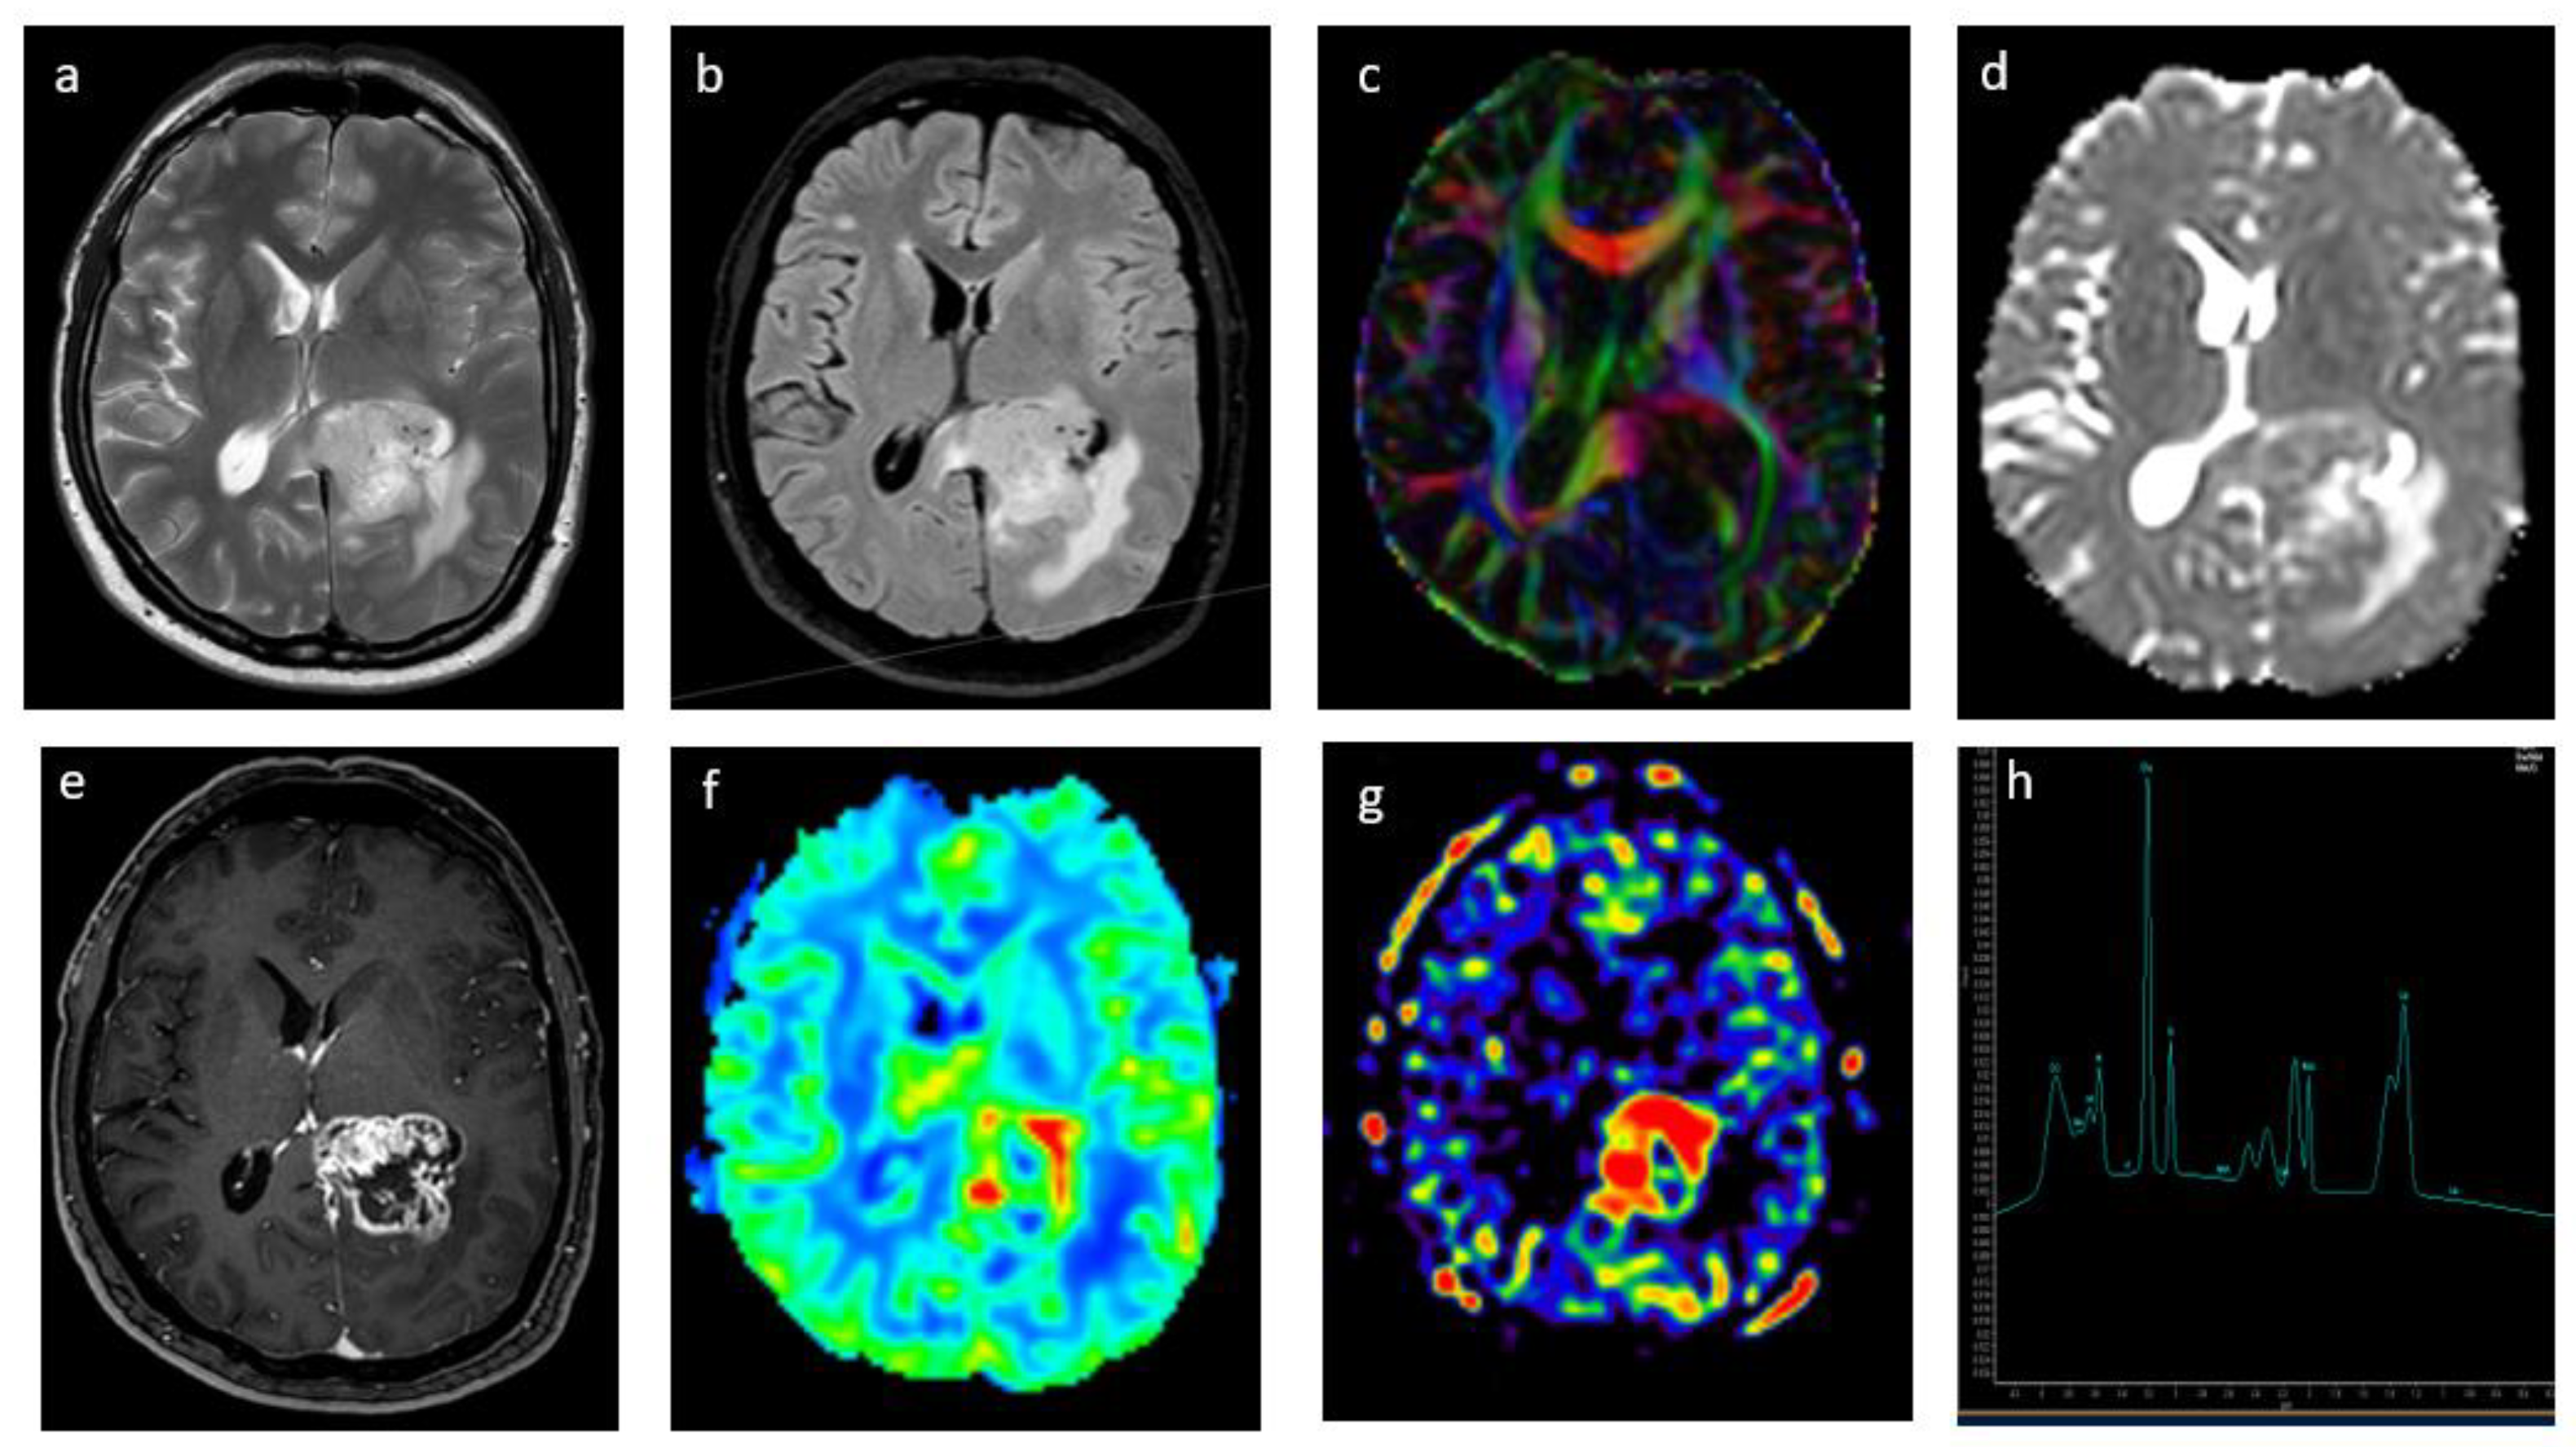

2.2. Diffusion-Weighted and Diffusion Tensor Imaging

2.3. Perfusion Imaging

2.4. Dynamic Susceptibility Contrast Perfusion

2.6. Arterial Spin Labeling

3.1. Glioma Grade Classification

3.2. Correlation with Glioma Molecular Profile

5.1. Radiation Necrosis Versus Tumor Recurrence